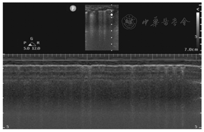

已有大量研究证实,肺滑动征消失是诊断气胸最关键的征象[15,18]。在二维超声难以准确评估胸膜运动时,需结合其他超声技术做出准确诊断。正常情况下,M型超声能够清晰显示肺滑动征,呈现"沙滩征"(图3)。气胸时由于肺滑动征消失,M型超声显示胸膜线下方的颗粒样点状回声被一系列平行线所替代,即"平流层征"或"条码征"(图4)。M型超声显示"沙滩征"与"平流层征"截断处即为肺点。M型超声不仅可用于寻找肺点,还可指导和评价气胸的治疗。胸腔引流时要在离肺点较远的位置插管,以获取更好的排气效果,此时可用M型超声评价胸腔引流效果,若"沙滩征"替代"平流层征"则表明插管排气有效。